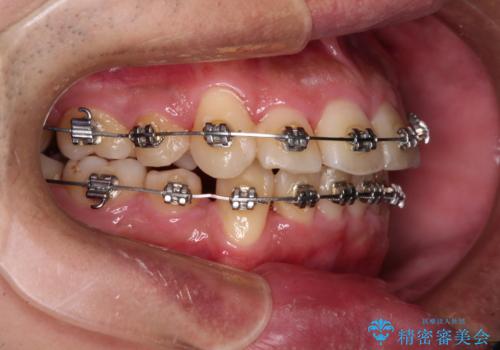

- メタルブラケット

- 3年10ヶ月

- 30回以上

右上第一小臼歯は歯根癒着により移動せず、左上第二小臼歯は移動はするものの非常に動きが鈍かったため、抜歯したスペースを閉じるまでに非常に時間がかかってしまいました。

患者様には辛抱強く治療にお付き合いいただき、すっきりとした口元に仕上げることができました。